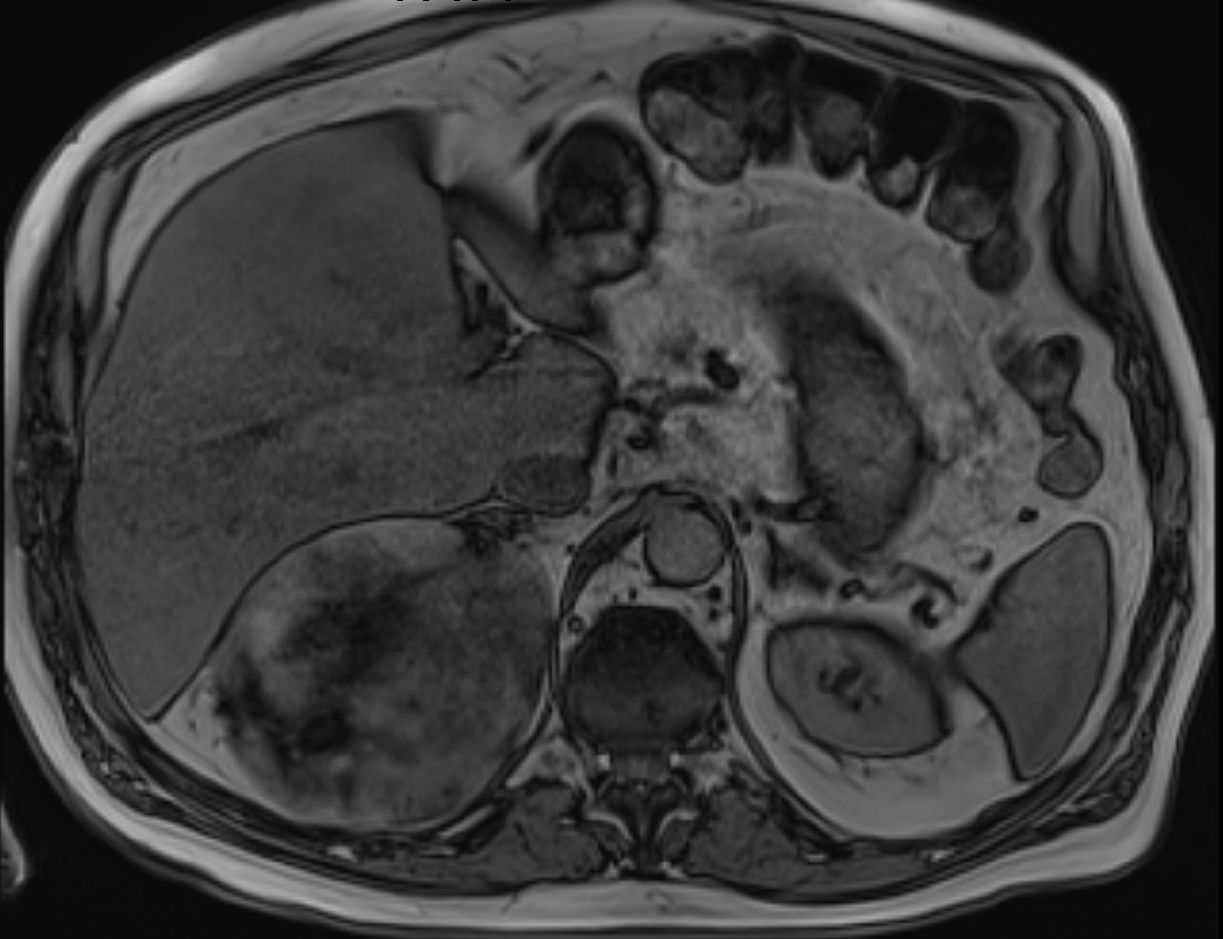

79-jähriger berenteter, adipöser Fleischer mit respiratorischer Insuffizienz. Urothel-Ca vor 15 Jahren. Jetzt kleines Bronchial-Karzinom. Beim Tumorstaging wurde ein großer NN-Tumor rechts entdeckt. | |||

![]() |